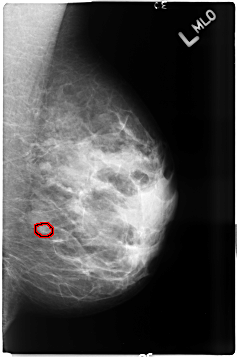

B_3497_1.LEFT_MLO

LEFT_MLO LINES 4640 PIXELS_PER_LINE 3072 BITS_PER_PIXEL 12 RESOLUTION 50 OVERLAY

FILE: B_3497_1.LEFT_MLO.OVERLAY

TOTAL_ABNORMALITIES 1

ABNORMALITY 1

LESION_TYPE CALCIFICATION TYPE PLEOMORPHIC DISTRIBUTION CLUSTERED

ASSESSMENT 4

SUBTLETY 3

PATHOLOGY BENIGN

TOTAL_OUTLINES 1

BOUNDARY